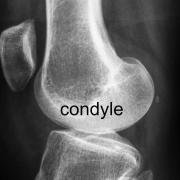

With the knee bent, the key components of the femur within the knee joint can be seen, and include -

- the two rounded condyles - the condyles bear the body weight through the knee joint.

- the trochlear groove between the condyles where the kneecap runs

- the intercondylar notch between the condyles towards the back of the knee, which houses and protects the important cruciate ligaments.